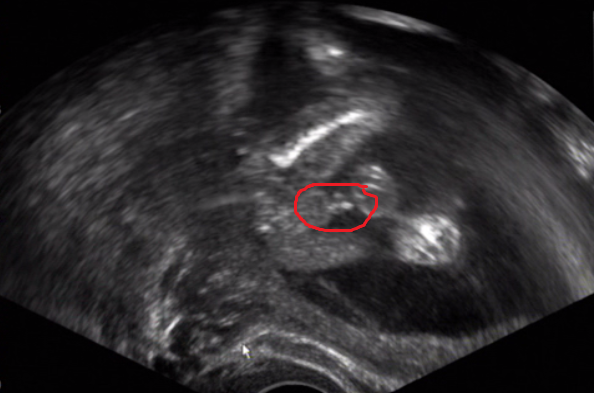

Ahoj holky,dlouho jsem se neozvala,13.4. Jsem sla na rehospitalizaci s hematomem do nemocnice,a od te doby tu lezim,bohuzel se mi hematom dvakrat mezi kontrolama zvetsil uz je 66mm na 19mm a navic je tak vlbe,ze hrogi odchlipnuti placenty:( takze lezim,smim jen na wc a na jidlo a jsem uz k.o. naposledy mi delali utz v pondeli a od te doby nic,tak doufam,ze ho po tydnu zopakujou,zacinaji se mnou cvicit hormony,vcera jsem asi hodinu brecela,kdyz

[893227] hlavne klid,s hematomem sem byla ve spitalu 14 dni,zvetsil se,pak se velikost ustatlila tak me s lekama a narizenym klidem pustili domu,mela jsem ho 55x16mm pak pak se zmensil na 25x9mm potom jsem zacla trochu krvacet tak sup do nemocnice hematom je ted 36x13,fakt to cce lezet jak mi trochu otrne a zacnu se vic hybat zacnu krvavet a hematom se zvetsovat